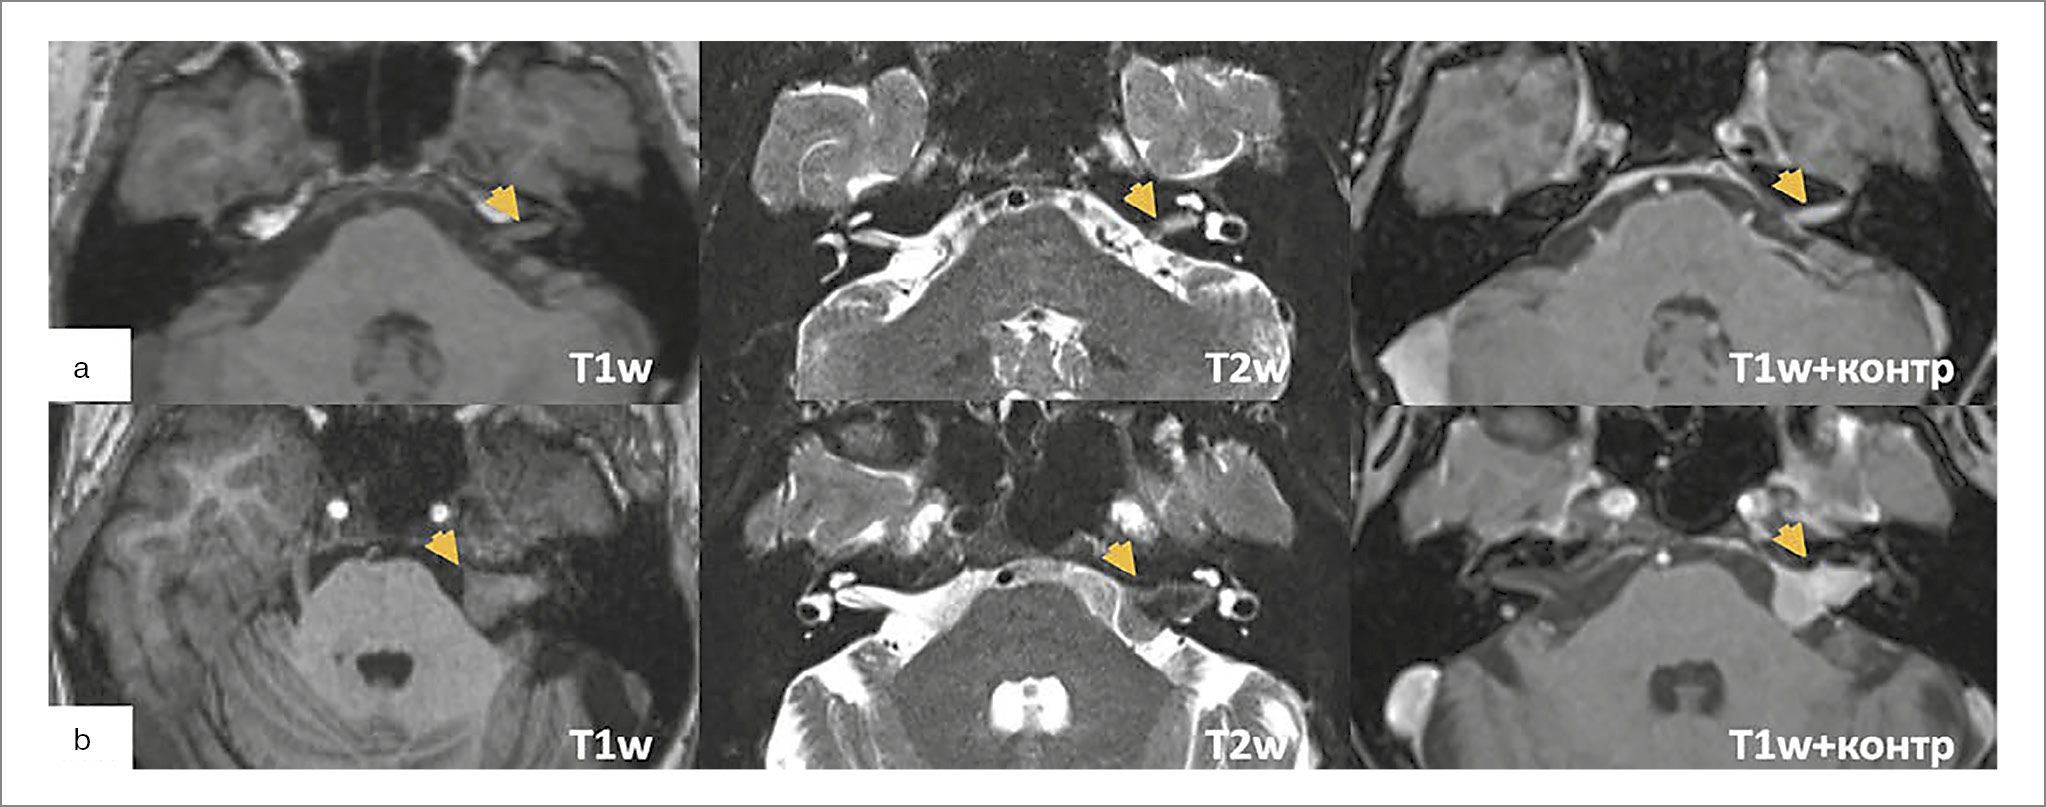

Диагностика ВШ складывается из анализа клинико-анамнестических (снижение слуха, шум в ухе, вестибулярные нарушения, дисфункция мимической мускулатуры лица, снижение чувствительности лица, головные боли и пр.), аудиологических данных и результатов компьютерной томографии (КТ) и МРТ (рис. 1). КТ головного мозга – метод, не специфичный для данной патологии, однако позволяет предоперационно оценить особенности анатомии височных костей. При больших новообразованиях наиболее характерный КТ-признак – конусобразное расширение ВСП с одной стороны.

Рис. 1. МРТ-исследования пациентов с ВШ: а – интраканальная опухоль левого ВСП; b – новообразование левого ВСП Т2 по классификации Koos; опухоль заполняет всю мостомозжечковую цистерну, доходит до ствола; c – новообразование правого ВСП Т4 по Koos; опухоль оттесняет структуры ствола, сдавливает ликвороотводящую систему (зеленая стрелка). Здесь и далее на рис. 2–4 желтой стрелкой указан патологический процесс.

МРТ (не менее 1,5 Т) – метод выбора для выявления ВШ, при этом Т1-взвешенные изображения (тонкосрезовые спин-эхо или турбо-спин-эхо) с контрастным усилением считаются «золотым стандартом» как при установке диагноза, так и в периоде наблюдения [17, 18]. Протокол МРТ должен включать стандартные Т1- и Т2-взвешенные последовательности, диффузионно-взвешенные изображения (DWI) и режимы с жироподавлением. Режим non-EPI DWI полезен для дифференциации ВШ от арахноидальных или эпидермоидных кист. По крайней мере одна Т2-взвешенная последовательность обязательна, чтобы исключить возможную патологию ствола мозга, имитирующую симптомы ВШ (глиомы, рассеянный склероз) [18]. Аксиальная субмиллиметровая высокоинтенсивная Т2-взвешенная последовательность наиболее важна для оценки нервов ВСП [визуализируются как линейные гипоинтенсивные структуры, окруженные гиперинтенсивной спинномозговой жидкостью в цистернах (FIESTA, CISS или DRIVE)].

При размерах новообразования менее 5 мм визуальные изменения структур ВСП по данным стандартного МРТ (Т1, Т2, Flair) чаще отсутствуют [19, 20]. Ранее сообщалось, что около ½ интраканальных ВШ локализуется в центральных отделах ВСП [21]. Однако, по последним данным N. Koen и соавт., имеется латеральное преобладание ВШ<5 мм (61% – в области дна ВСП, 34% – в средней трети, только 5% – в области внутреннего отверстия ВСП) [22]. При экстра-интрамеатальных опухолях на МРТ ММУ определяется симптом «рожка мороженого»: расширенный ВСП и шар в области мостомозжечковой цистерны (ММЦ). Характеристика в Т1-, Т2-режимах может варьировать в зависимости от наличия кистозного компонента. При введении контрастного препарата характерно его накопление в структуре опухоли.

Для понимания общей клинической картины при ВШ важна оценка местоположения и размеров опухоли, компрессии структур ствола мозга, сосудисто-нервных структур области и ликвороотводящей системы. Для классификации ВШ в настоящее время чаще всего используются классификации по A. Samii и по Koos, которые объединяют характерную МР-картинку и клиническую симптоматику.